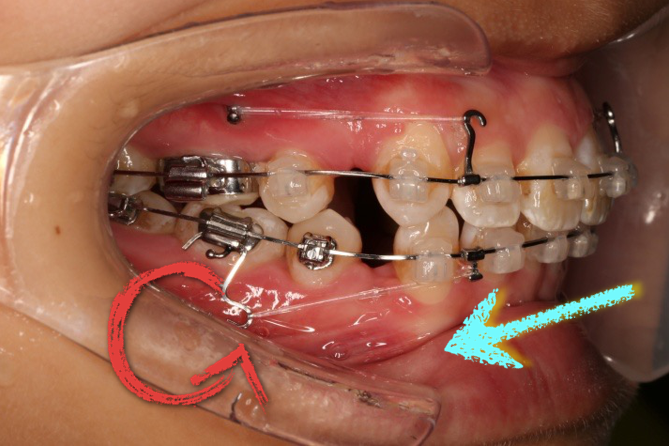

2018.5.25  (19个月)拆TPA,16、26粘tube 上颌0.14*25cu-niti  下颌0.018*25niti2018.7.23  上颌 0.017*25TMA,下颌0.017*25ss43压低曲,双侧后牙垂直牵引

2018.09.29  15、43、16、17、11、21重粘,上0.016*25cu-niti 下0.018niti 上连扎

长时间使用TPA或者使用颌内支抗关间隙,容易造成第一磨牙和第二磨牙颚侧尖出现台阶,容易造成术后早接触及咬合关系不良

(引用其他病例图片)